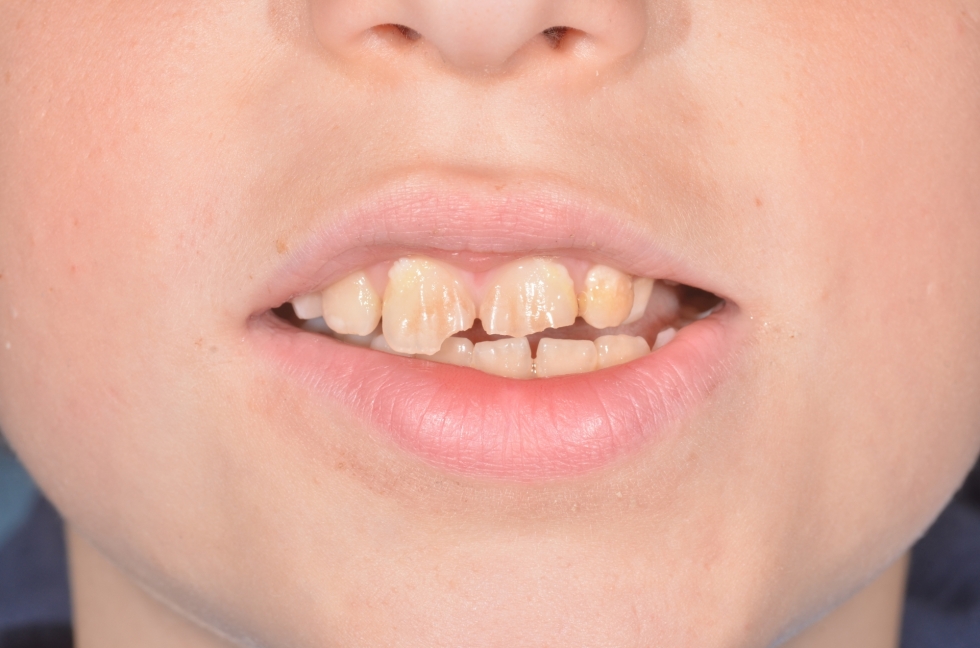

ESTETICA DENTALE NEI BAMBINI

si tratta di una bambina di 11 anni con una malformazione conoide degli incisivi laterali.

il sorriso mostra spazi e denti in malposizione

paricolare degli incisivi laterali a forma conoide

i due incisivi sono stati ricostruiti provvisoriamente in materiale compopsito in attesa della dentizione definitiva.